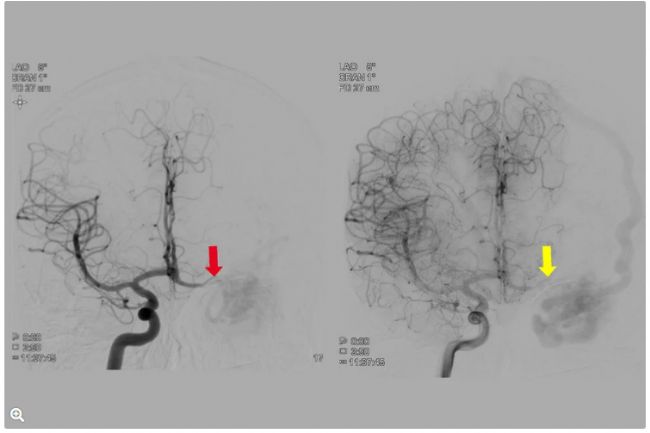

術前評估圖像 - 盜血

圖7:AP投影?梢杂^察到對側頸動脈系統(tǒng)(紅色箭頭)和同側大腦前動脈(黃色箭頭)中的血管盜血。